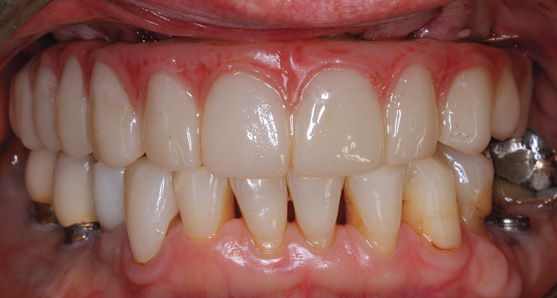

The workflow described in this case is just one example, and there are numerous ways to achieve the same goal. This particular workflow is relatively easy to execute and efficient from the standpoint of planning, fabrication, and clinical application. Figure 11 and Figure 12 demonstrate the accurate placement of the implants as can be seen by the copings exiting directly into the openings in the printed provisional. The provisional was indexed and the copings picked-up by injecting a provisional bisacryl composite resin. The finished 3D-printed provisional was characterized with pink composite and fixated to the implants with abutment screws, and the access holes were sealed with sterilized teflon tape and composite resin (Figure 13).

The rigidly fixated provisional was left undisturbed for a minimum of 5 months to allow for osseointegration of the implants. The patient was advised to maintain a soft diet during that time. To prevent fracture of the provisional, cantilevers should be eliminated or minimized and any metal inserts should have at least 4 mm of thickness around them. If any fractures or chips have occurred on the provisional they can be repaired intraorally or extraorally with standard light-cured bisphenol A-glycidyl methacrylate (bis-GMA) or bisacryl composite resins. Figure 14 and Figure 15 illustrate the in-house 3D-printed provisional at 5 months with excellent bone levels on the implants.

Fig 13. Retracted view after immediate delivery of characterized provisional prosthesis.

Figure 13

Fig 15. CBCT x-rays 5 months post-surgery.

Figure 15